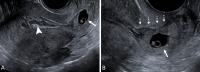

The Society of Radiologists in Ultrasound convened a multisociety panel to develop a first-trimester US lexicon based on scientific evidence, societal guidelines, and expert consensus that would be appropriate for imagers, clinicians, and patients. Through a modified Delphi process with consensus of at least 80%, agreement was reached for preferred terms, synonyms, and terms to avoid. An intrauterine pregnancy (IUP) is defined as a pregnancy implanted in a normal location within the uterus. In contrast, an ectopic pregnancy (EP) is any pregnancy implanted in an abnormal location, whether extrauterine or intrauterine, thus categorizing cesarean scar implantations as EPs. The term pregnancy of unknown location is used in the setting of a pregnant patient without evidence of a definite or probable IUP or EP at transvaginal US. Since cardiac development is a gradual process and cardiac chambers are not fully formed in the first trimester, the term cardiac activity is recommended in lieu of 'heart motion' or 'heartbeat.' The terms 'living' and 'viable' should also be avoided in the first trimester. 'Pregnancy failure' is replaced by early pregnancy loss (EPL). When paired with various modifiers, EPL is used to describe a pregnancy in the first trimester that may or will not progress, is in the process of expulsion, or has either incompletely or completely passed. © RSNA and Elsevier, 2024 Supplemental material is available for this article. This article is a simultaneous joint publication in Radiology and American Journal of Obstetrics & Gynecology. All rights reserved. The articles are identical except for minor stylistic and spelling differences in keeping with each journal's style. Either version may be used in citing this article. See also the editorial by Scoutt and Norton in this issue.